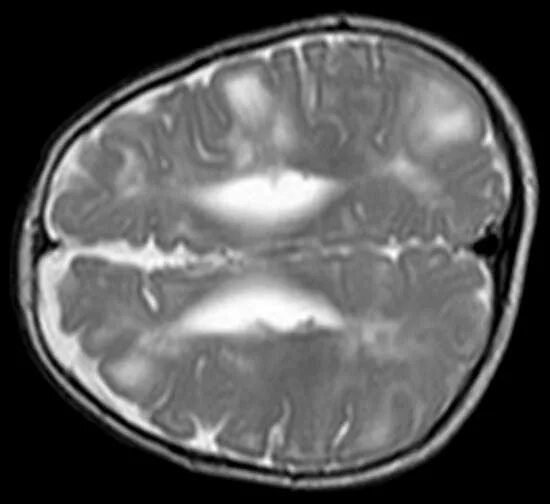

Ребенок асимметрия боковых желудочков